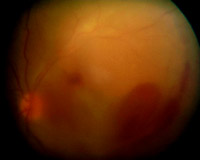

Presentamos el caso clínico de una mujer sana de 30 años que presenta una disminución brusca de la AV del OI. A la exploración presentaba una AV en el ojo derecho (OD) de 1 y en el OI de cuenta dedos a 50 cm, con escotoma central, observándose en el fondo de ojo del OI una hemorragia subhialoidea de grandes dimensiones (4 diámetros papilares verticales por 6 horizontales) (

Figura 1) que se extendía por encima de la arcada temporal inferior hasta el área macular; no se apreciaban otras alteraciones del fondo en el OI ni en el OD.

Figura 1. Hemorragia subhialoidea macular de grandes dimensiones